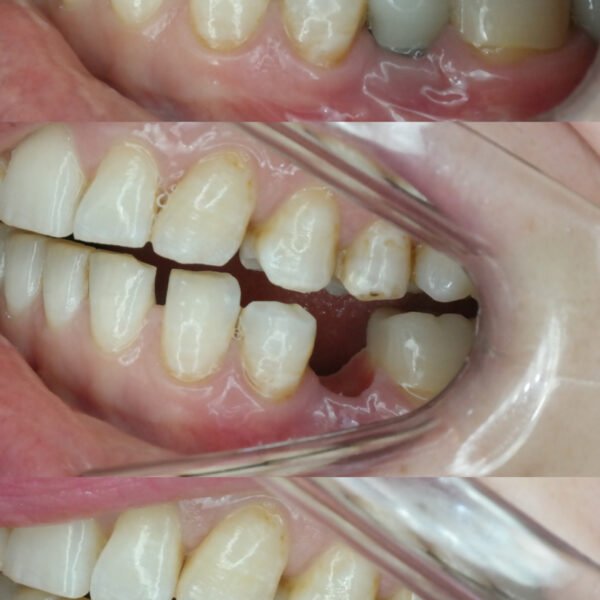

Diş İmplantı Bakımı

İmplant tedavisi sonrası hastanın doğal dişleriyle birlikte implantların temizliğine gerekli özeni göstermesi implantların ömrü açısından son derece önemlidir. İmplant sonrası ağız bakımı hekim tarafından hastaya öğretilmeli ve hasta 3 aylık periyodik kontrollere gelmelidir.